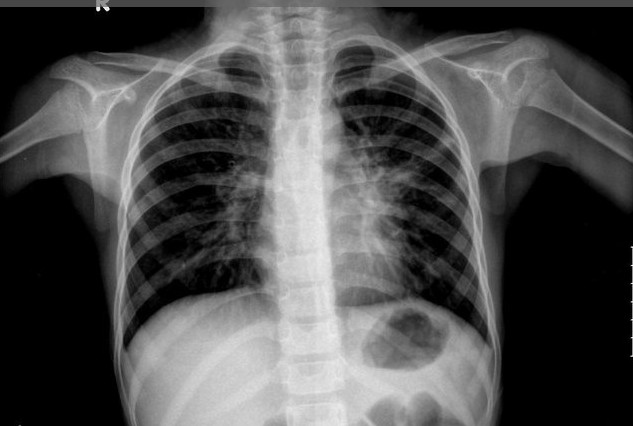

结核菌素试验多为强阳性,X线胸片表现为哑铃型阴影,及原发病灶、引流淋巴管炎和肿大的肺门淋巴结,形成典型的原发综合征。若X线胸片只发现肺门淋巴结肿大,则诊断为胸内淋巴结结核。肺门淋巴结结核可呈团块状、边缘清晰和密度高的肿瘤型或边缘不清、伴有炎性浸润的炎症型。